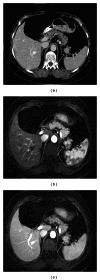

Spleen can have a wide range of anomalies including its shape, location, number, and size. Although most of these anomalies are congenital, there are also acquired types. Congenital anomalies affecting the shape of spleen are lobulations, notches, and clefts; the fusion and location anomalies of spleen are accessory spleen, splenopancreatic fusion, and wandering spleen; polysplenia can be associated with a syndrome. Splenosis and small spleen are acquired anomalies which are caused by trauma and sickle cell disease, respectively. These anomalies can be detected easily by using different imaging modalities including ultrasonography, computed tomography, magnetic resonance imaging, and also Tc-99m scintigraphy. In this pictorial essay, we review the imaging findings of these anomalies which can cause diagnostic pitfalls and be interpreted as pathologic processes.